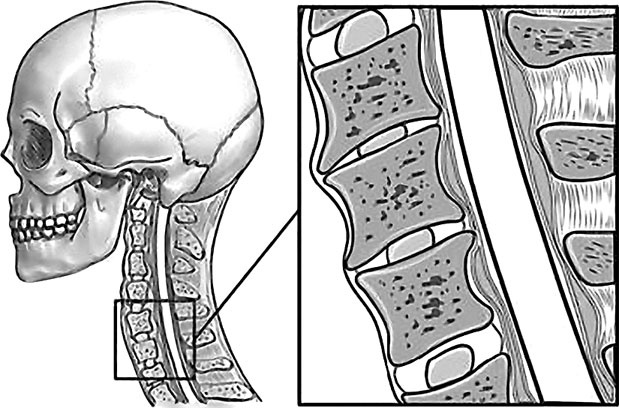

Вторит ему Говард Лэнгстайн (Howard Langstein), руководитель службы пластической и реконструктивной хирургии в университетской клинике: «Резорбция костной массы приводит к потере былой четкости овала и к провисанию мягких тканей. Внешне это проявляется в том, что нижняя часть лица приобретает более мягкие овальные очертания, снижается тонус кожи щек, подбородка и шеи, в результате чего очертания лица приобретают характерный возрастной вид». Далее Г. Лэнгстайн заявил: «Хотя врачи всегда знали, что кости со временем меняются, но как это проявляется с возрастом – не оценили». В свою очередь остеопороз черепа напрямую зависит от кровоснабжения головы. И мы опять приходим к неизбежности хорошего состояния «трубопроводов», несущих питание к мозгу и лицу. А перекрываться это питание может не только из-за сжатия артерий, но и всех сосудов шейного отдела, в том числе и вен. В этом случае артериальная кровь будет поступать, а отток будет заблокирован, что вызовет повышение внутричерепного давления и сильную головную боль. Головной мозг снабжается из двух сосудистых бассейнов. Первый составляют сонные артерии. Поражение этих артерий часто приводит к развитию острого нарушения мозгового кровообращения (инсультам). Ко второму относятся правая и левая позвоночные артерии. Их поражение не приводит к таким тяжелым осложнениям, как инсульт, но может способствовать головокружениям, усиливающимся при движениях головы или изменении положения тела. Подобные симптомы могут вызываться спазмами как позвонков, так и мышц шеи. К примеру, перенапряжение затылочных мышц зачастую ведет к головным болям и к проблемам со зрением. Так что шейный отдел позвоночника, состоящий из 7 позвонков, должен иметь и достаточную длину, и определенную статику (рис. 67). ![]() Рис. 67. Нормальная статика шеи. Правильный физиологический изгиб: А=А1 А что в действительности имеем мы? Обычно, даже при здоровом позвоночнике (только где его найдешь?), он начинает с возрастом деформироваться, «проседать», менять статику. Появляется симптом смещенной вперед и запрокинутой назад головы (рис. 68). ![]() Рис. 68. Гиперлордоз шейного отдела позвоночника: B > B1 В результате небольшой физиологический изгиб гипертрофируется, что ведет к проваливанию шейных позвонков вглубь шеи, особенно интенсивно при «сидячей» работе. Формируется гиперлордоз шейного отдела позвоночника. Чаще всего виной тому является не возраст, не тяжесть гравитации, а элементарно наша плохая осанка: сутулость, неправильная статика шеи, опущенная вниз голова, когда попытка смотреть в глаза собеседника достигается взглядом исподлобья за счет запрокидывания головы назад. Посмотришь на лицо, вроде бы женщина еще молодая, ухаживающая за собой. А взглянешь со стороны – прямо старушка ковыляет – ссутулилась, шейка вперед подалась, плечики сжались. Хорошо, сама себя не видит, а то бы очень огорчилась. Из-за того, что с возрастом диски между позвонками уплощаются, длина шеи укорачивается и частенько весьма значительно (рис. 69). ![]() Рис. 69. Шейный отдел позвоночника Появление поперечных морщин и складок на боковой поверхности шеи служит точной приметой этого явления. Проведите тесты – проверьте свою шею на ее статику – физиологический изгиб. Вот тут вам и пригодится второе зеркальце. 1. Возьмите его и внимательно рассмотрите свою шею в профиль и особенно сзади, приподняв волосы. Не стоит удивляться тому, что, возможно, там вы ее вообще не найдете – слишком коротким будет расстояние от первого позвонка до последнего – 7-го шейного, который легко прощупывается. В идеале длина шеи должна быть одинаковой по всей ее окружности. Если вам больше 40 лет, будьте готовы к тому, что, измерив свою шею, вы найдете сзади не более 2–3 см своей шеи. 2. Если запрокинуть голову назад, появляется ощущение, что в основание головы упирается кол – это ваш 7-й позвонок упирается в первый. Закономерно напрашивается вопрос: «А куда делись оставшиеся 5?» – запали внутрь шеи. И как бы ни было ухожено лицо, ни о какой молодости говорить уже не приходится. 3. Сравните длину вашей шеи с «эталонной». Похоже? Или…? Скорее всего или… Чтобы восстановить свою шею, недостаточно лишь массажами убрать жир с так называемой «холки» (кстати, основная часть этого горбика не жир, а отек лимфы) и «разбить остеохондрозные соли». В первую очередь необходимо восстановить статику шейного отдела. Ведь не «вытащив» запавшие вглубь шеи позвонки, характеризующие гиперлордоз шеи, вам никогда не приобрести четкого овала. При этом проблемы статики шейного отдела не ограничиваются возрастным гиперлордозом шейного отдела, когда шейные позвонки проваливаются вглубь шеи (рис. 70). Частенько, наоборот, этот изгиб может быть и излишне спрямлен (рис. 71). ![]() Рис. 70. Гиперлордоз шейного отдела ![]() Рис. 71. Спрямление шейного отдела позвоночника А вот для молодого поколения, особенно в наше время тотальной компьютеризации, характерен третий дефект неправильной статики шеи, который я назвала «компьютерной шеей» (рис. 72). Провоцируясь в большей степени именно вытягиванием шеи к экрану монитора, он выражается в ее вытянутости вперед и тоже сопровождается избыточным грудным кифозом – сутулой осанкой. ![]() Рис. 72. «Компьютерная» посадка шеи При такой статике центр тяжести головы (ЦТ) смещен вперед относительно центра тяжести тела (рис. 73). |